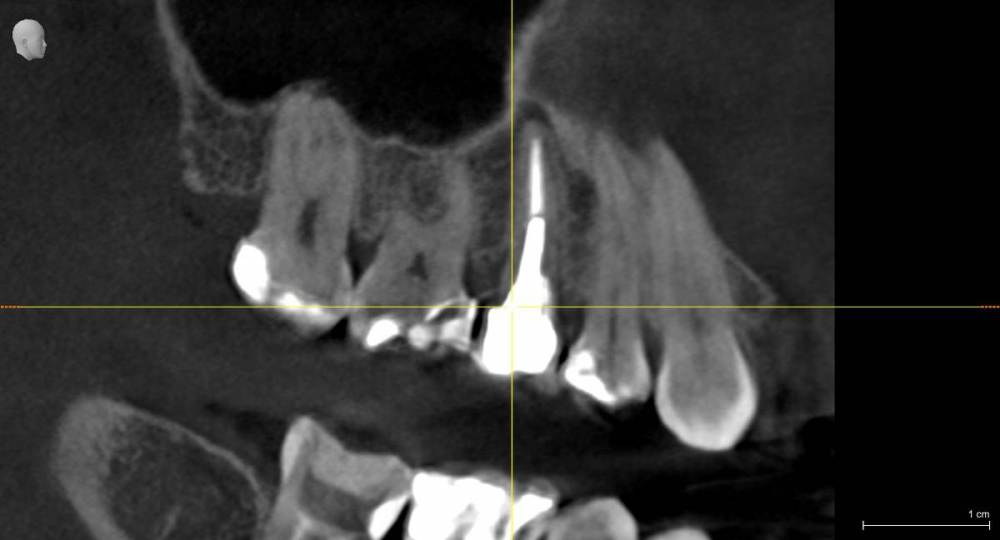

Три месяца назад стала болеть десна верхнего зуба возле коронки (пятый), только с внутренней стороны , но при этом все время языком хотелось трогать соседний зуб( 4). Врач ничего не увидела, сказала полоскать. На давление, холод, постукивания зуб с коронкой и соседние не реагировали. Через какое то время возникло ощущение что 4 верний зуб как будто вырос и немного подвижет, на что врач ответил что я выдумываю, предложил поменять пломбы на соседних зубах, но лучше не стало. Сделала КТ, опять ничего не видят. Ко всему этому добавилась головная боль и усталость. на десне, с внутренней стороны, выше к нёбу между 6 и 7 зубами  выскочила шишка,если сильно нажать то болит, а так нет, выделений нет.  сделали рентген, опять мне говорят, что все ок. На мой вопрос , что это за круги на рентгене, ничего не ответили, к сожалению забыла взять последнюю фото, но на первом прицельном фото этот круг уже виден, на новом больше кругов и они распространились дальше на 6, 7   зубы. На панорамме видно как новооброзование. Погите понять что это?

Прицельное фото в марте  делала, КТ в мае. А новое фото забыла взять.

Iljaseviciene_Lina_3D examination(3)_VO1_20210507_090920_Longitudinal.jpg